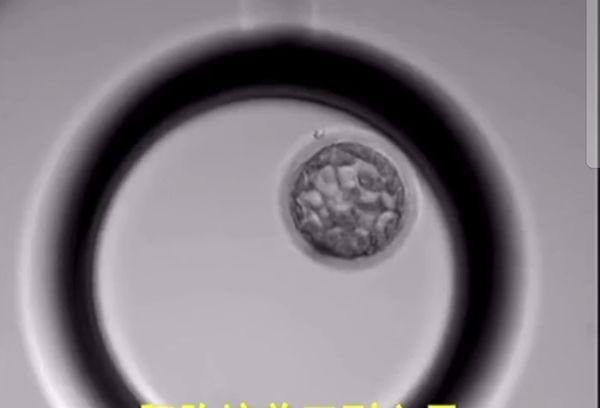

胚胎培养第5-6天:胚胎继续发育,中间形成一个囊腔,故取名囊胚。囊胚移植就是用这个时期的胚胎宝宝哦!